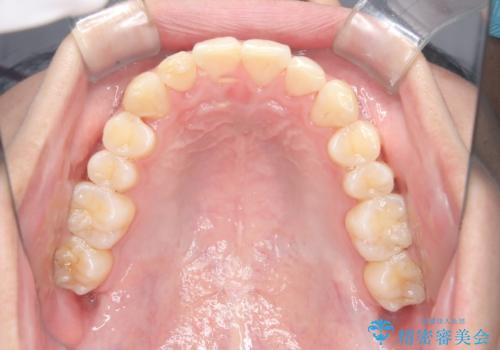

インビザラインにて、遠心移動を行いながら綺麗に配列することができました。

側切歯が低位の場合、反対咬合を改善した後に挺出させるのはワイヤーの方が適しています。